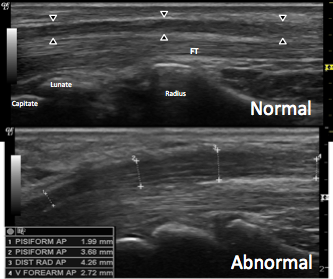

신경의 염증 뿐만 아니라,

손목 관절의 염증

인대, 힘줄의 염증을

동반하는 경우가 많아

관절-인대-힘줄 상태에 따라

치료가 달라지게 됩니다.